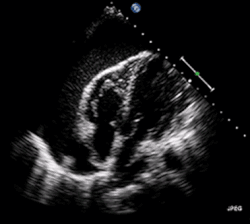

ECG: may present with sinus tachycardia, low voltage QRS as well as electrical alternans.[2] Due to the fluid accumulation around the heart, the heart is further away from the chest leads, which leads to the low voltage QRS. Electrical alternans signifies the up-and-down change of the QRS amplitude with every beat due to the heart swinging in the fluid (as displayed in the ultrasound image in the introduction) .[1] These three findings together should raise suspicion for impending hemodynamic instability associated with cardiac tamponade.

Echocardiogram (ultrasound): when pericardial effusion is suspected, echocardiography usually confirms the diagnosis and allows assessment of the size, location and signs of hemodynamic instability.[4] A transthoracic echocardiogram (TTE) is usually sufficient to evaluate pericardial effusion and it may also help distinguish pericardial effusion from pleural effusion and MI. Most pericardial effusions appear as an anechoic area (black or without an echo) between the visceral and the parietal membrane.[1] Complex or malignant effusions are more heterogeneous in appearance, meaning they may have variations in echo on ultrasound.[5] TTE can also differentiate pericardial effusion based on the size. Although it's difficult to define size classifications because they vary with institutions, most commonly they are as follows: small <10, moderate 10–20, large >20.[5] An echocardiogram is urgently needed for evaluation when there is concern for hemodynamic compromise, a rapidly developing effusion or history of recent cardiac surgery/procedures.[1]

A large anechoic (black) pericardial effusion as seen on ultrasound. Closed arrow: the heart, open arrow: the effusion -